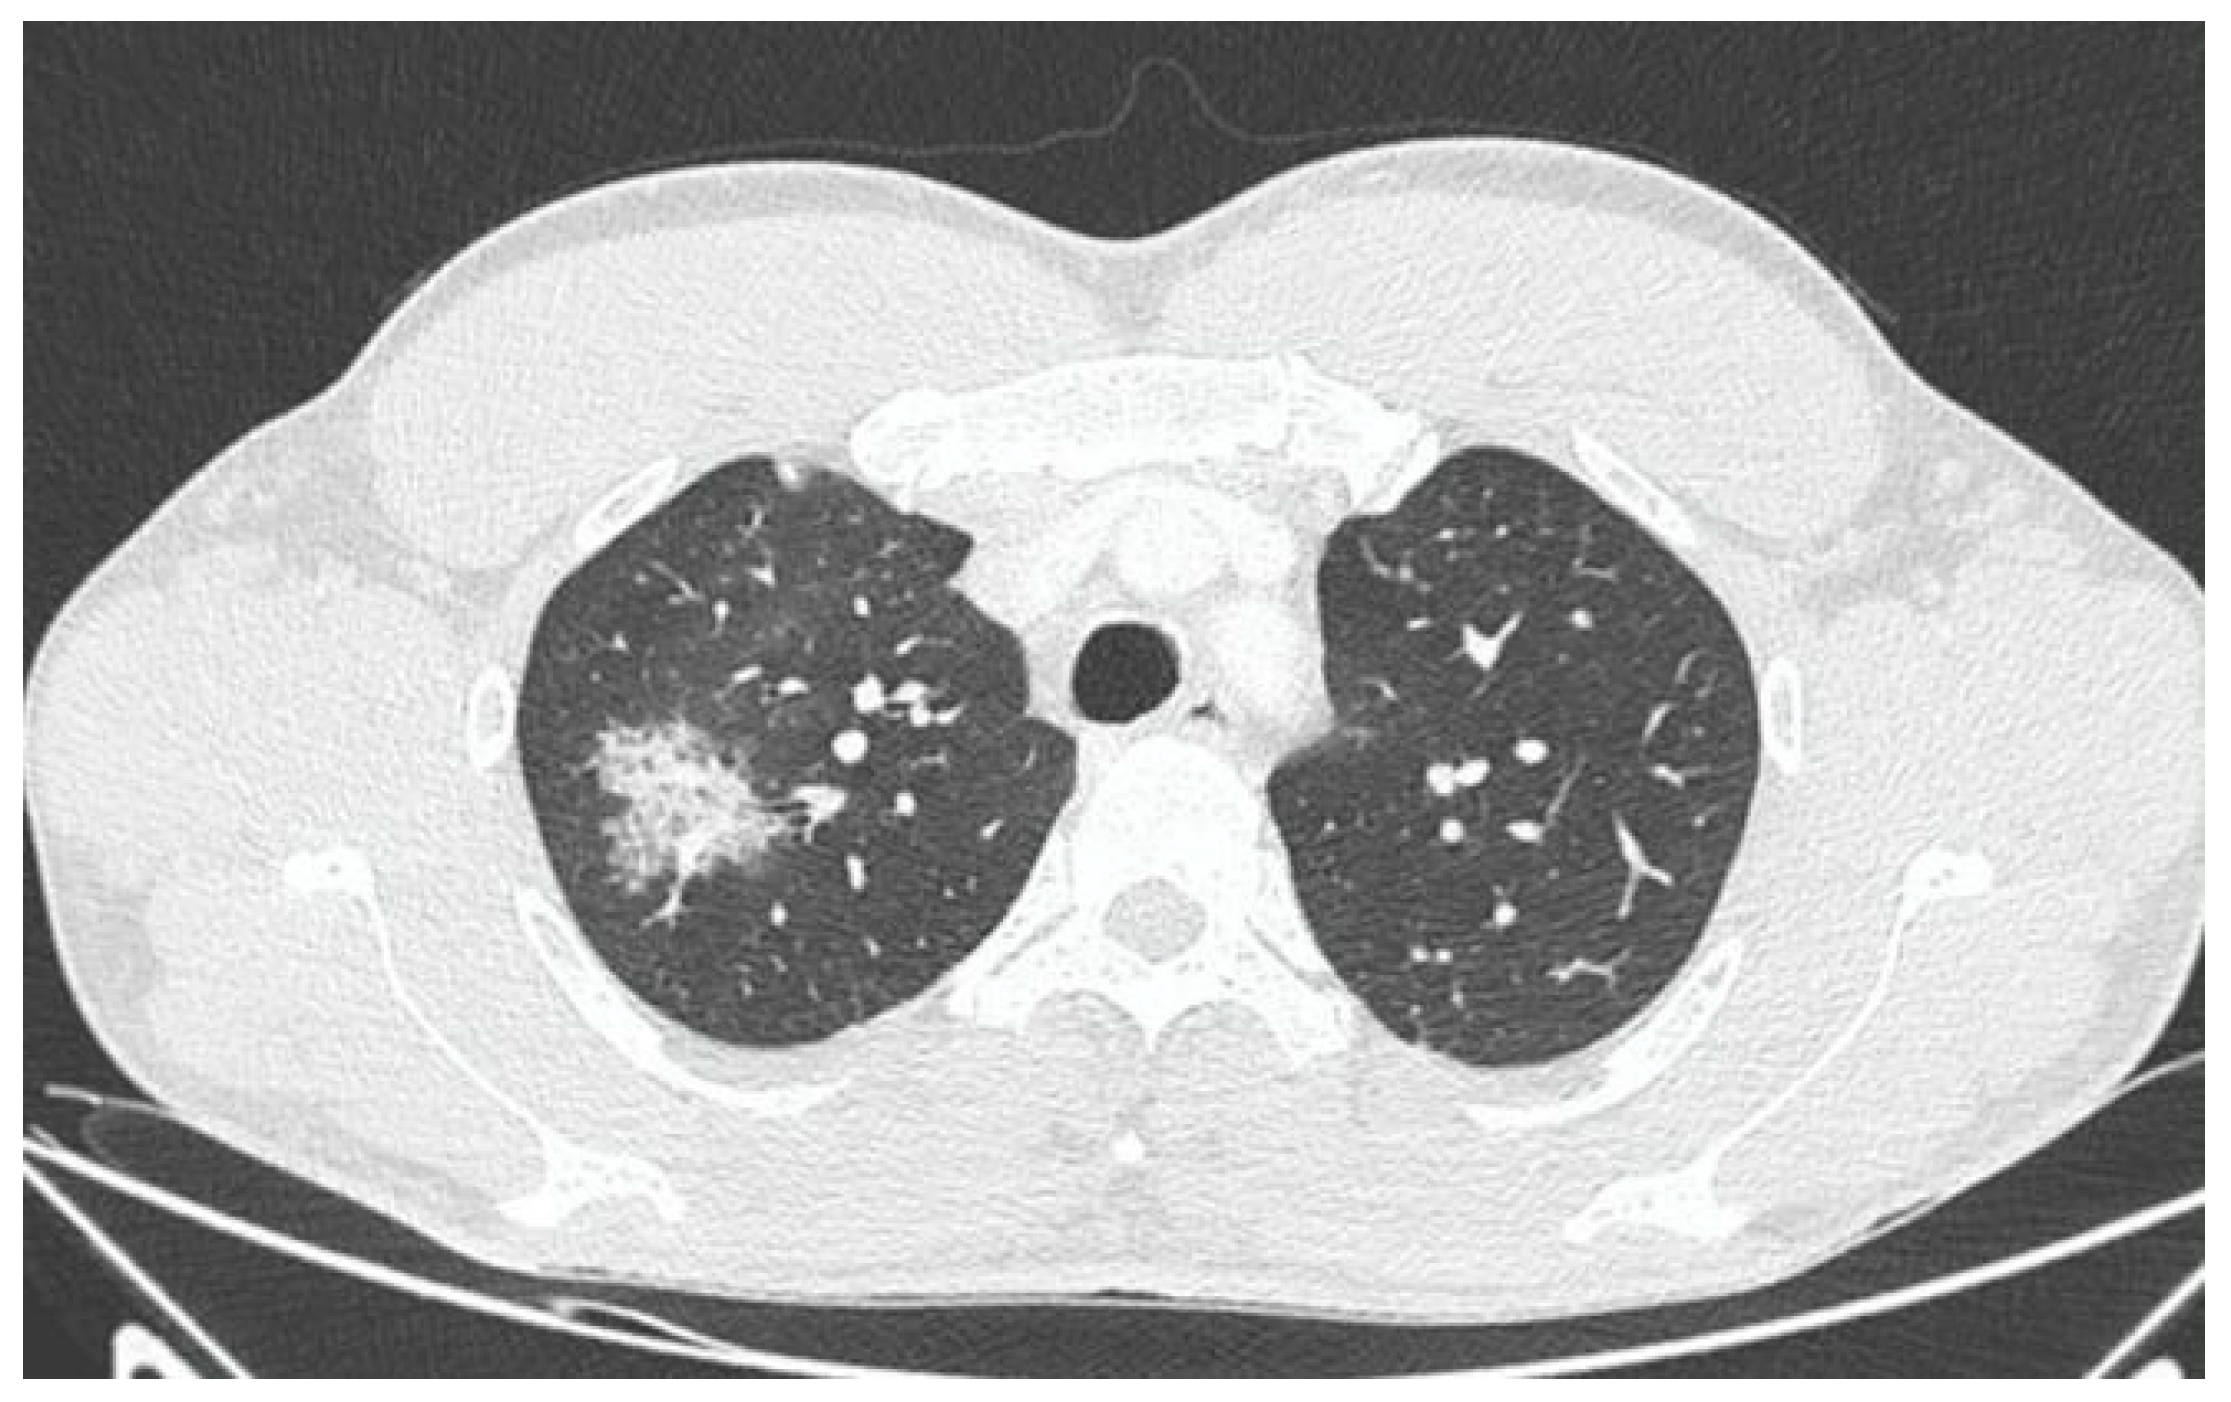

X-ray and CT scans of the chest were performed. The left lung’s lower lobe infiltrates and the right lung’s upper lobe interstitial changes (most probably of an inflammatory nature) were shown, as well as a small amount of fluid in the left pleural cavity (Figure 3 and Figure 4). Several tests were also performed to determine the etiology of the pneumonia. However, blood cultures, an antigen test for SARS-CoV-2, urine tests for Streptococcus pneumoniae, Legionella pneumophila, Cryptococcus sp., and Mycobacterium tuberculosis antigens, and an HIV screening test were all negative. In the following days, empirical antibiotic therapy with ceftriaxone and vancomycin was continued. A rapid improvement in the patient’s clinical condition was observed, as well as a significant decrease in the levels of inflammatory markers. On 22 August 2022, the patient was discharged home in good general condition.

Figure 4. CT scan of the chest showing right lung upper lobe interstitial changes during first hospitalization.

In this paper, we posed the question of whether there is a possible link between the initial infection and the subsequent occurrence of pulmonary disorders in the patient. Monkeypox viral pneumonia is one of the more commonly described complications of this disease in humans and can be associated with significant mortality [7,8,9,10,11]. Goff et al. published the results of an animal study (on primates), which concluded that monkeypox pneumonia can be lobular or interstitial pneumonia of viral etiology or can be caused by bacterial superinfection [10]. In the case we described, pneumonia occurred after the symptoms of the initial infection had already resolved and most likely was of bacterial etiology. Although it was not possible to identify any specific pathogen, bacterial etiology is supported by the overall clinical picture and, above all, the rapid resolution of symptoms after the administration of antibiotics. However, we cannot exclude the superposition of viral and bacterial pneumonia (in particular, bacterial superinfection of a primary viral infection). This possibility may be indirectly indicated by the heterogeneous radiological picture. In X-ray and CT scans, inflammatory lesions were visible in both lungs. However, while in the left lung, they were described as lobular pneumonia, in the right lung, there was an area of likely interstitial inflammatory lesions. It should be mentioned that the literature indicates that bacterial superinfection can exacerbate the symptoms of monkeypox viral pneumonia [10,12].

CT scanIn the lower lobe of the left lung, an area of infiltrative changes with an air bronchogram of inflammatory changes is visible. An irregular, non-homogeneous circular area of interstitial changes with a diameter of 3 cm is visible in the upper lobe of the right lung. Probably inflammatory changes. In the right apex, a second similar lesion with a diameter of 1.5 cm is visible subpleurally.